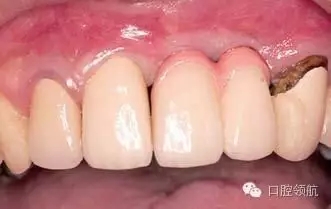

患者,53歲,男性,(右上第1、2顆牙) 缺失病例,由于牙槽骨高度不足,在行髂骨移植后進(jìn)行了種植手術(shù),但由于移植骨的吸收,種植體周圍的牙槽骨形態(tài)發(fā)生了變化引起了與對側(cè)同名牙的齦曲線明顯不對稱(圖1)。

圖1 去除愈合基臺后,由于移植骨的吸收,種植體周圍骨組織形態(tài)產(chǎn)生變化,引起與對側(cè)同名牙齦曲線明顯不對稱,作為解決的方案,提出通過外科手術(shù)再植骨和軟組織移植的方法以改善嵴頂?shù)拿缹W(xué)形態(tài)或使用修復(fù)方法來改善軟組織的美學(xué)效果。以上兩種方法供患者參考,最后患者選擇了修復(fù)的方法。

可以選擇在(右上第1、2顆牙) 部位的唇側(cè)進(jìn)行結(jié)締組織移植來獲得牙齦組織美學(xué)形態(tài)連續(xù)性的恢復(fù)的外科方式。在本病例中,因為患者不是露齦笑的類型,所以選擇了用修復(fù)的辦法提高美學(xué)效果,在金屬基底冠上,使用牙齦瓷,來恢復(fù)牙齦形態(tài)對稱性(圖2、圖3)。

圖3 戴入有牙齦瓷的金屬基底烤瓷冠,(右上第3顆牙) 是不良修復(fù)體,計劃在(右上第1、2顆牙)種植區(qū)周圍的軟組織穩(wěn)定后,再對(右上第3顆牙) 進(jìn)行重新修復(fù)。